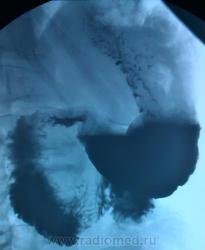

Мужчина, возраст в районе 50. Искали язву. За качество снимков извиняюсь, но сбросить на диск категорически не получается...

UPD: Первые 4 снимка сделаны в пределах 10 минут, последний - через 1,5 часа.

UPD 2: Пациент был проооперирован. Злокачественная опухоль тощей кишки, гистологию не уточняла. Честно скажу, что диагноз был поставлен не верно, правильный ответ всего лишь прозвучал в контексте: "не, ну не может же это рак быть". Основной теорией был АМК, ну и более популярные, чем рак, варианты, которые многие из вас отметили.

Что смутило:

1. Странный какой-то желудок на первом снимке. По одному нему мог бы предположить инфильтративный рак.

2. Четко не увидел контуров большой кривизны желудка ни на одном снимке.

3. Деформация складок в верхней половине тела желудка и их сглаженность в угле и выходном отделе(рисунок1).

4. Но главная проблема наверное в тощей кишке(рисунок2)?

Желудок действительно странный. В просвете большое количество слизи. Или пациент нарушил подготовку, т.е. зубы почистил, выпил водички и т.д. Горизонтальная часть синуса и антрального отдела, как будто снизу чем -то подпирает. Складки сглажены. Признак артерио-мезентериальной компрессии есть, другое дело выражен он функционально. Данный АМК характерен не только истеричным женщинам, но и спокойным, а также и мужчинам. Тощая кишка расширена, и в ней тоже большое количество жидкости.

ИМХО: как уже сказали коллеги, расширение просвета тощей кишки, видимо по причине нарушения нормального пассажа, то же в 12-перстной кишке, можно преположить , что есть какая-то причина вне тощей кишки, например опухоль брюшной полости. Показано УЗИ органов брюшной полости. Компрессия 12-перстной кишки верхнебрызжеечной артерией есть, но это может быть конституционального характера, у худых. По методике исследования- все снимки сделаны в вертикальном положении, это не правильно- надо было посмотреть и в горизонтальном положении, многие вопросы ( в частности у нас) может быть и отпали бы. Вообще, это отдельная тема для разговора, говоря коротко можно резюмировать, что те рентгенологи которые пренебрегают этим правилом, пилят сук на котором сидят.